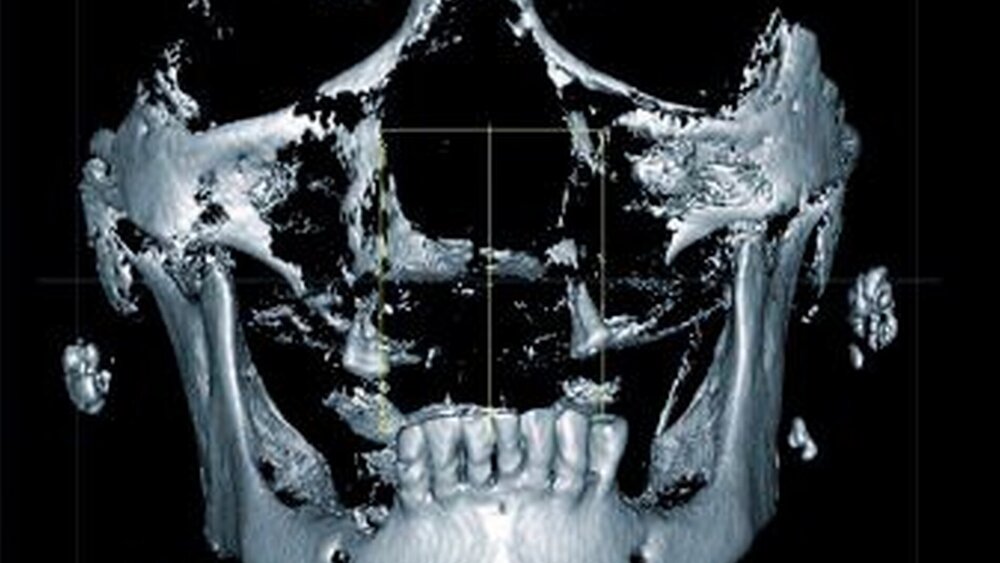

Zur genauen räumlichen Zuordnung der Verschattungen unterhalb der Incisurae semilunares wurde eine dentale digitale volumentomografische Untersuchung durchgeführt (Abbildungen 2 bis 4).